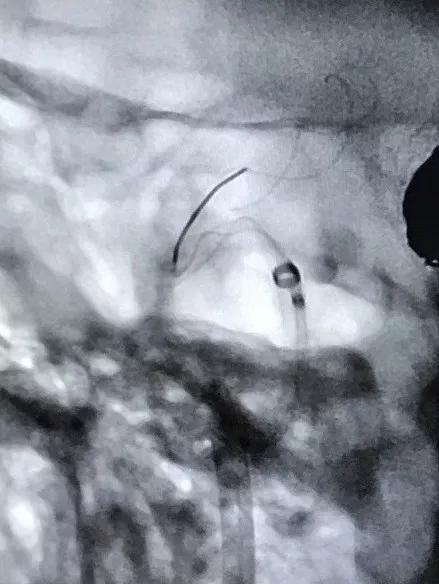

再行右侧颈内动脉血流导向装置置入术:将8F Envoy导引导管置入右侧颈总动脉,105cm 6F Navien导引导管头端置入颈内动脉岩骨段,造影见海绵窦段3个动脉瘤,由近及远直径一次为5mm、8mm、9mm,颈内动脉床突上段可见一大小约为5×4mm的宽颈动脉瘤。

通过导引导管,在Synchro2微导丝的配合下将T-track微导管置入右侧大脑中动脉。

选择4.0×15mm Tubridge®支架,成功释放,覆盖颈内动脉床突上段动脉瘤。